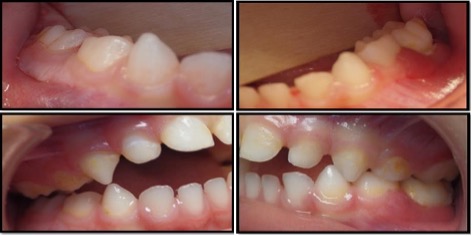

En el 2014, un dentista privado refirió a un paciente masculino de 3 años a la clínica de la Residencia de Odontopediatría de la Escuela de Medicina Dental de la Universidad de Puerto Rico, para evaluar una posible enfermedad periodontal en los segundos molares inferiores primarios1. El examen intraoral reveló una inflamación en la gingiva de los lados izquierdo y derecho, a nivel de los segundos molares inferiores primarios, obliterando el ángulo mandibular (Figura 1). Otros tejidos orales aparecieron dentro de los limites normales. En esa primera visita, luego del examen clínico, se obtuvo una radiografía panorámica la cual reveló una perdida ósea bilateral en los segundos molares primario derecho e izquierdo mandibular. La lesión del lado izquierdo mostraba un patrón radiolúcido extenso de márgenes irregulares desde el segundo molar primario hacia el folículo del primer molar permanente, desplazándolo posteriormente y creando una apariencia de dientes flotantes.1 El paciente recibió intervención quirúrgica con biopsia excisional y curetaje de las áreas afectadas con extracción de los segundos molares mandibulares primarios y el folículo del primer molar mandibular permanente izquierdo. Los especímenes obtenidos tanto del lado derecho como izquierdo mandibular fueron consistentes con Histiocitosis de Células de Langerhans. Posterior a este diagnóstico, el paciente fue referido al servicio de hematología/oncología para evaluación y tratamiento. Una tomografía computarizada fue ordenada la cual reveló que también había lesiones menores en el hígado y el área abdominal. El paciente fue tratado posteriormente con quimioterapia. Durante 3 años, el paciente continuó un protocolo riguroso de seguimientos dentales cada 3 meses con un dentista pediátrico y cada 6 meses con una cirujana maxilofacial. En el 2017, el seguimiento reveló en la radiografía panorámica y radiografía de mordida, una radio lucidez periapical del primer molar primario izquierdo envolviendo el primer premolar permanente. Debido al historial previo se tomó la decisión de realizar una segunda intervención en sala de operaciones donde se extrajeron el primer molar primario izquierdo y el folículo del primer premolar permanente izquierdo. El resultado de esa biopsia reveló un folículo dental agrandado y células inflamatorias sin evidencia de recurrencia de la lesión previa. En seguimiento, el paciente ha presentado exámenes clínicos y radiográficos periódicos sin evidencia de lesiones recurrentes. En el último seguimiento en el 2019, no reveló nuevas lesiones y el paciente se encontraba asintomático. La Figura 2, resume la toma de radiografías panorámicas durante el periodo de 2014 a 2019.

Figura 1. Fotografías intraorales. Las imágenes intraorales muestran encía enrojecida e inflamada alrededor del segundo molar primario mandibular derecho. Inflamación localizada y apariencia hemorrágica de la encía en la superficie facial de los molares primarios mandibulares izquierdos y la retención de placa generalizada también se nota en la mayoría de los dientes del paciente.